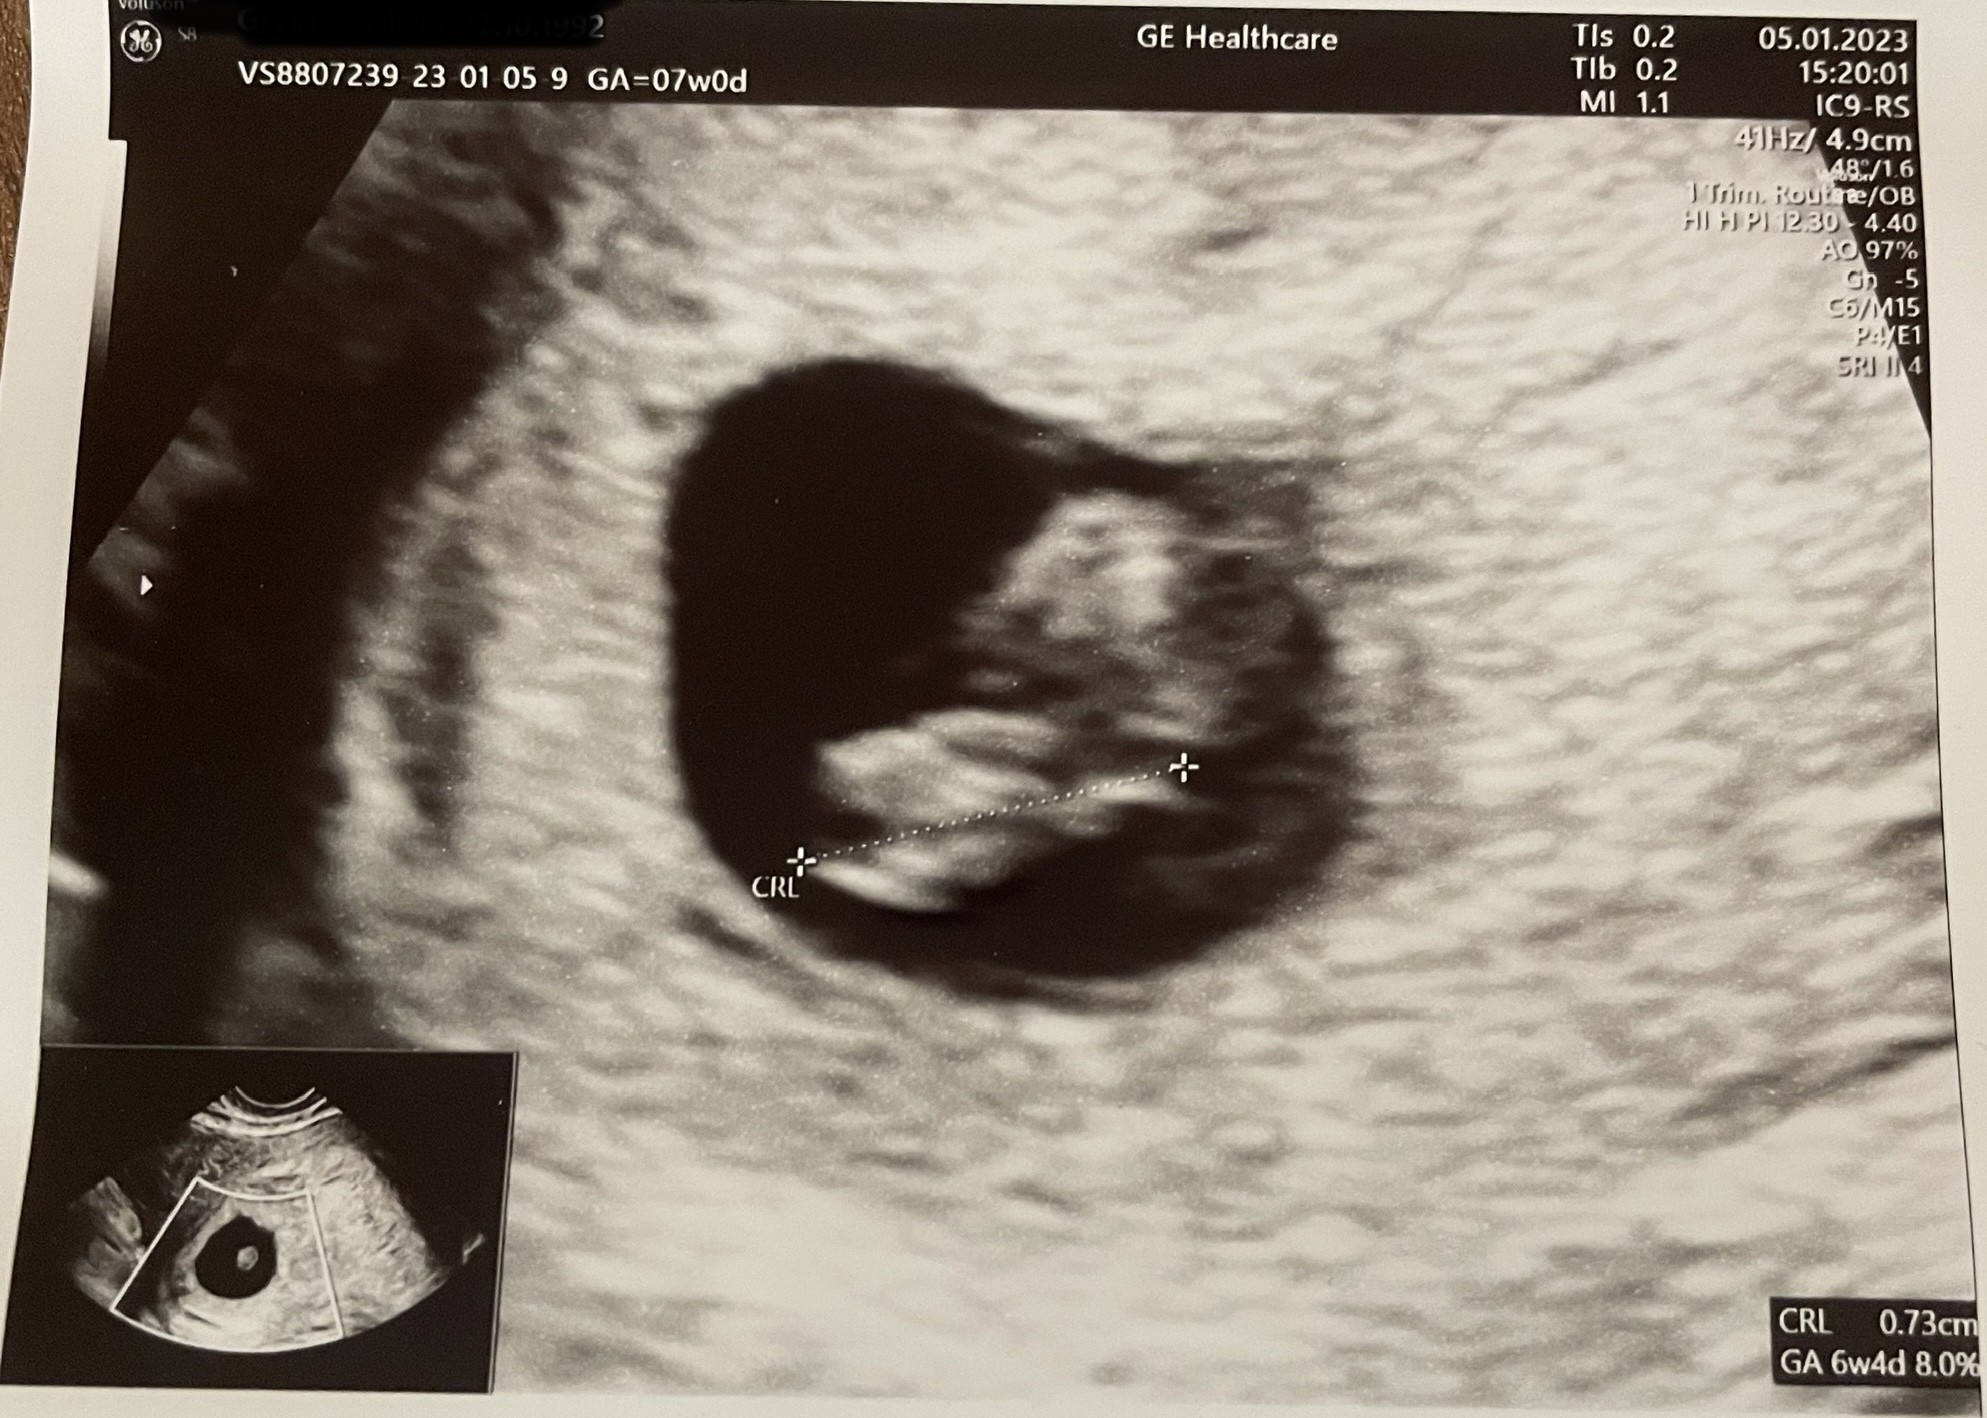

Wszystko jest w porządku, słyszałam serduszko, to piękny dźwięk. Maluch ma 0,75 cm. Założono mi kartę ciąży, dostałam tez duphaston, bo delikatnie nieregularna kosmowka jest.

Kolejna wizyta za 3 tyg ;)

Za wiele nie widać na tej fotce. Chodziłam już do mojej p. Doktor wcześniej i kojarzę, ze był dobry sprzęt a tu jakiś taki rozmazany obraz nie wiem dlaczego. Ale dodaje :)

Załączniki

• ED865A6A-663B-4CD9-B220-9A4A8E7DA715.jpeg

ED865A6A-663B-4CD9-B220-9A4A8E7DA715.jpeg

530,1 KB · Wyświetleń: 118